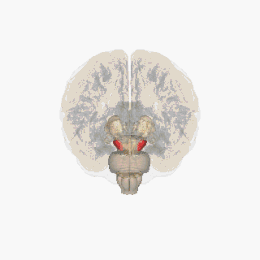

Le diagnostic de maladie de Parkinson est habituellement clinique. En théorie, la certitude du diagnostic n'est obtenue que par l'étude histologique du cerveau mais les critères diagnostiques actuellement définis permettent de faire le diagnostic sans trop de difficultés. Le scanner cérébral par tomodensitométrie des personnes atteintes de la maladie de Parkinson est habituellement normal[123]. L'imagerie par résonance magnétique sensible au fer (IRM T2*) peut être utilisée dans un cadre diagnostique. En effet, le fer peut être témoin de la mort cellulaire et le signal T2* diminue en présence de fer tandis que son inverse (R2*) augmente[124]. Dans la maladie de Parkinson, il existe une concentration en fer trop importante par rapport à la moyenne pour le même groupe d'âge au sein de la substance noire du fait de la perte de neurones dopaminergiques[125]. De plus, l'imagerie pondérée en fonction de la susceptibilité est elle aussi un marqueur fiable de la présence de fer intracérébral en étant à la fois sensible et spécifique à la maladie[126]. L'IRM T2* et l'imagerie pondérée en fonction de la susceptibilité sont toutes deux capables d'afficher le signe d'effacement de la queue d'hirondelle (swallow tail) dans la substance noire dorsolatérale. La tomodensitométrie et l'IRM sont également utilisées, en pratique clinique, pour écarter d'autres maladies pouvant engendrer un syndrome parkinsonien telles que l'encéphalite, les AVC chroniques, les tumeurs des ganglions de la base et l'hydrocéphalie[123].